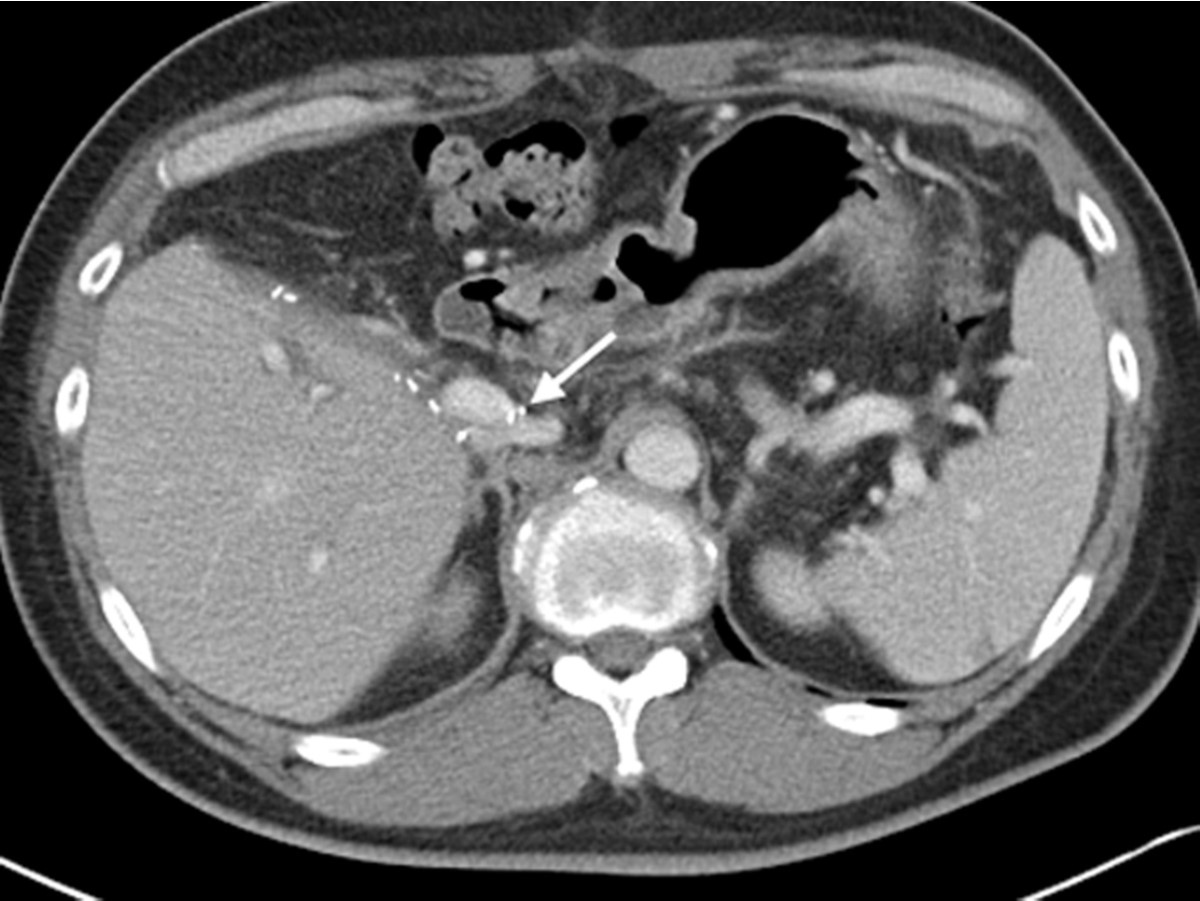

수술 전 CT에서 liver cirrhosis와 함께 S6에 1.9cm 크기의 HCC가 관찰되어 LDLT를 받았다. 수술 14일 후 시행한 abdomen enhanced CT에서 left portal vein은 IVC와 연결되어 있고 (Fig. 1), right portal vein은 graft liver에 연결되어 있어 hemiportocaval shunt를 확인 할 수 있었다. Hepatic perfusion defect 나 ascites 등은 관찰되지 않았다.

Fig. 1.

Fig. 1. Portal phase of abdomen CT, after LDLT with haniportocaval shunt formation shows left portal vein connected to inferior vena cava (arrow). Note the metallic surgical materials around the shunt.